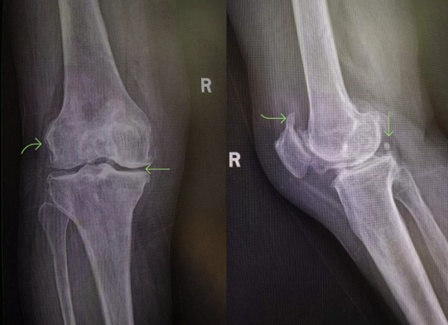

当您到医院就诊后,除了常规的“视、触、动、量”以外,医生一般会要求您拍摄一张X线片。X线是骨科疾病的最基本检查手段之一,也是骨关节炎影像学诊断的“金标准”。通常对于骨关节炎的影像学检查,往往无需CT、核磁共振(MRI),一张简单的X线平片即可明确。当然,MRI可显示关节软骨、半月板、交叉韧带、滑膜等关节软组织的情况,可以早期诊断和准确评价软组织的变性与损伤,是对X线检查的进一步补充。

这是膝关节骨关节炎典型的X线片,上图箭头所示右膝内侧间隙较外侧间隙明显狭窄,软骨下骨硬化;股骨、胫骨平台、髌骨上级边缘有增生的骨赘;侧位片显示关节后方有一枚关节内游离体。

图片引自骨关节炎诊疗指南(2021年版)